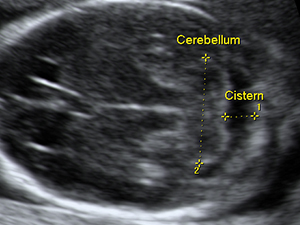

Second Trimester - Head and Face